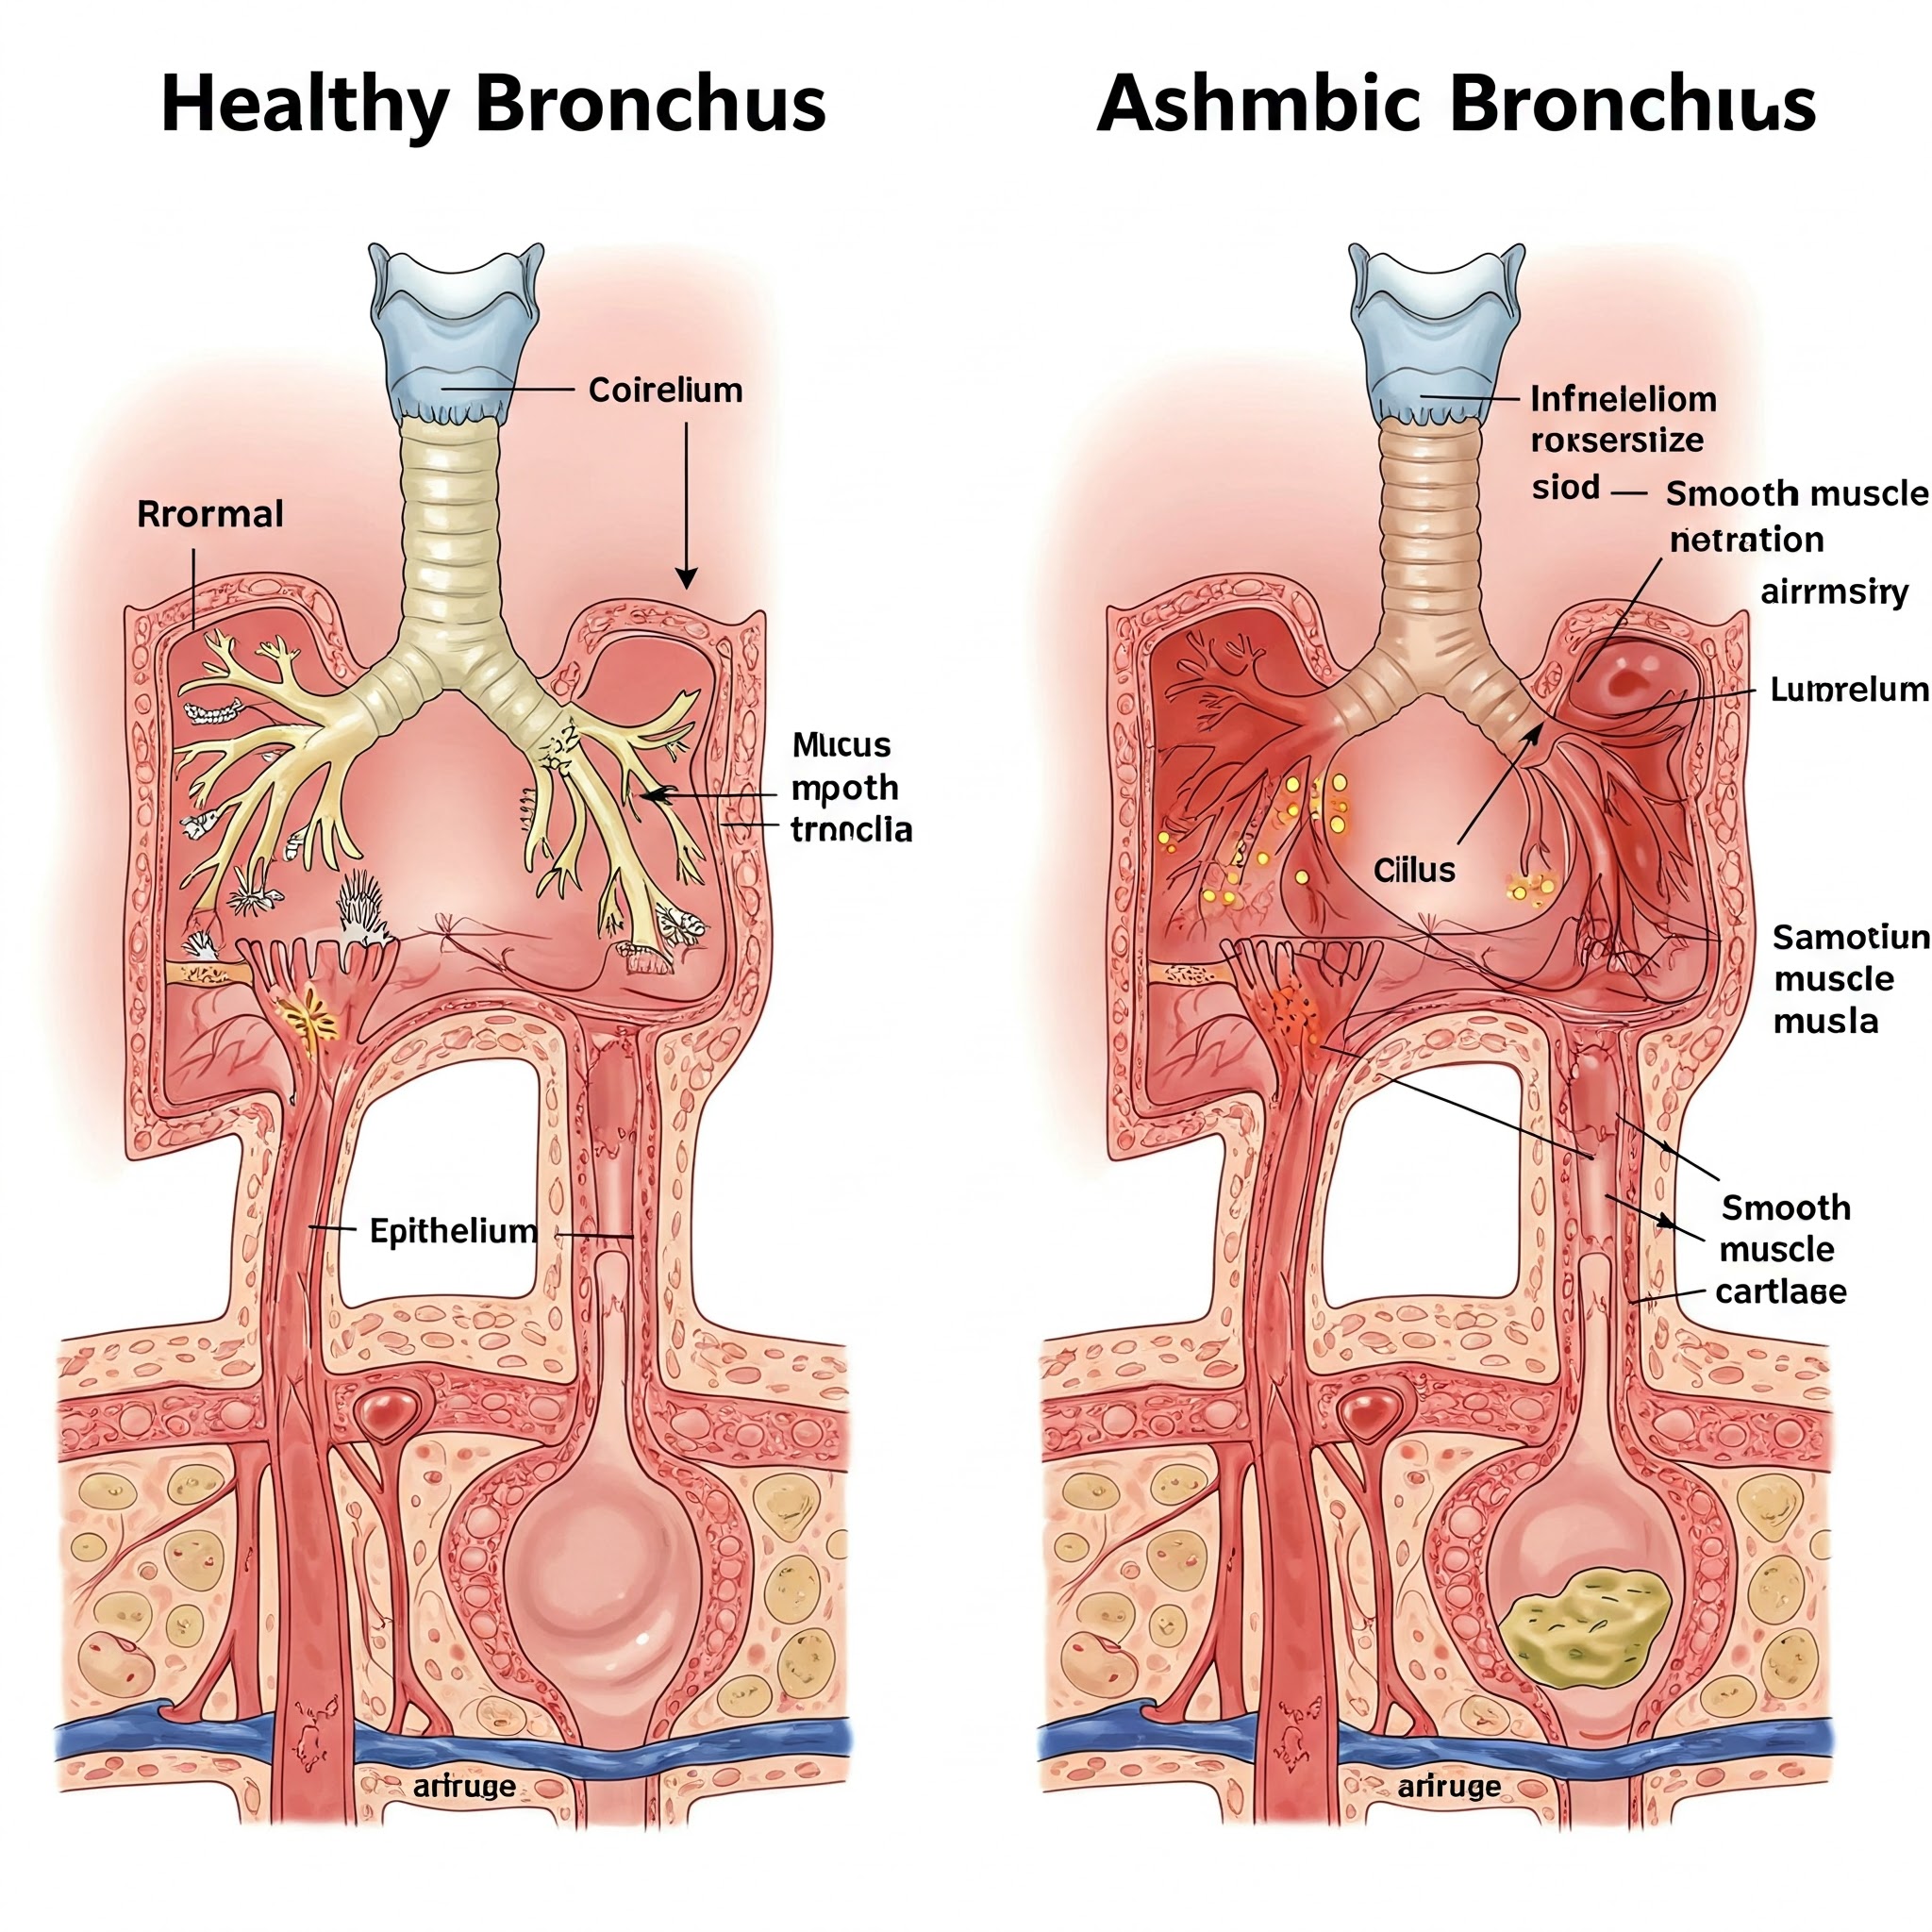

3.2. 천식: 기관지에 만성적인 염증이 생기면 기도가 좁아지고 예민해져서 기침, 숨쉬기 힘듦 (호흡곤란), 숨 쉴 때 쌕쌕거리는 소리 (천명) 등의 증상이 나타납니다. 마치 좁은 길을 지나갈 때 숨이 막히는 것처럼 느껴질 수 있습니다. 특히 운동 후나 밤에 증상이 악화될 수 있으며, 알레르기와 관련이 있는 경우가 많습니다.

천식: 흡입 스테로이드나 기관지 확장제 를 사용하여 기도의 염증을 줄이고 기도를 넓혀 호흡을 편안하게 해줍니다.